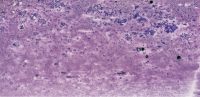

CAPFNA-2025-A 2-1.svs

27888 x 26976

@ 40X